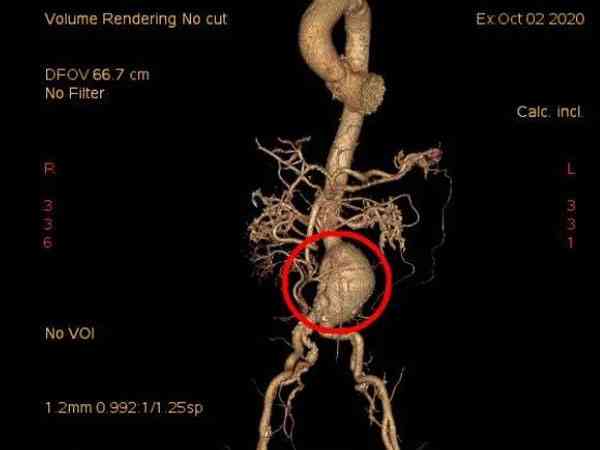

我和老公備孕好幾年懷不上,就打算做試管備孕,結果前期檢查的時候發現我有腹主動脈瘤,醫生讓我先治療,等病症緩解後再做進一步打算,我真的擔心這樣會做不了試管,想下有腹主動脈瘤能正常做過試管嬰兒嗎?會不會對胚胎移植造成影響?腹主動脈瘤對生育功能沒有明顯不良的影響,所以是能做試管嬰兒助孕的,對胚胎移植也不會有影響。不過在試管前最好是做腹主動脈瘤手術進行治療,在術後三個月之後再考慮備孕的相關事宜。手術一般是採取的開放式人工血管置換術和介入下支架植入術,這幾種方式對後期生孩子都不會造成太大的影響,手術治療後就可以正常備孕。

腹主動脈瘤是血管外科常見疾病,如果不進行治療腹主動脈管腔會持續增大,血管破裂的風險也會逐漸增高,一旦確診一定要及時手術治療。要不然一旦腹主動脈瘤破裂,會造成出血的現象,嚴重的還會危及生命健康,所以腹主動脈瘤最好是解除危險之後再妊娠會比較好。